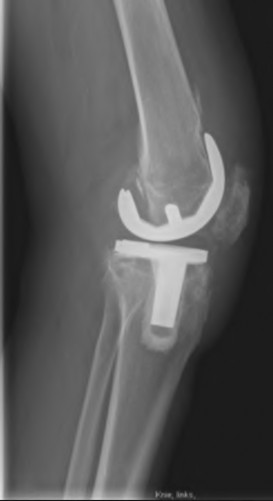

During a revision total knee arthroplasty, removal of the tibial component reveals a massive contained metaphyseal defect measuring 3 cm deep, but with an intact cortical rim. According to the Anderson Orthopaedic Research Institute (AORI) classification, what type of defect is this, and what is the preferred method of management?

During a complex revision TKA, the surgeon notes profound laxity and attenuation of the medial collateral ligament (MCL) such that the knee cannot be balanced coronally in either flexion or extension. The extensor mechanism and posterior capsule remain completely intact. Which level of prosthetic constraint is most appropriate in this scenario?

A 72-year-old patient undergoes a primary TKA for severe valgus deformity. Intraoperatively, the medial collateral ligament (MCL) is found to be severely attenuated and incompetent, preventing varus-valgus stability with standard gap balancing, but the extensor mechanism and soft tissue envelope are otherwise intact. Which level of implant constraint is most appropriate as the next step?